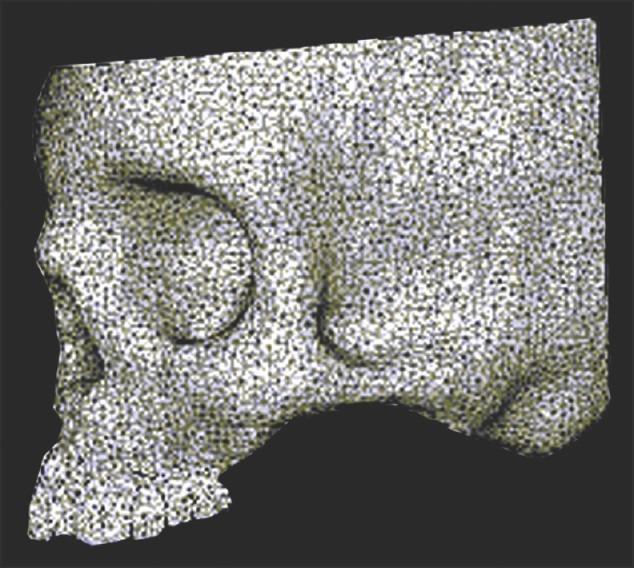

The Department of Orthodontics and Dentofacial Orthopedics at Government Dental College and Hospital, Nagpur. The study was done on an analytical model developed from a dry human skull of an adult female with an approximate age of 20 years.

A 3D finite element analysis of the craniofacial complex was developed from sequential computed tomography scan images. Known transversal (X) displacement with magnitudes of 1, 3, and 5 mm were applied and the displacement and Von-Mises stresses in different planes were studied on different nodes located at various structures of the craniofacial complex.

那格浦尔政府牙科学院和医院的正畸与牙颌面矫形科。该研究是在一个由一名年龄约20岁的成年女性干燥人类头骨开发的分析模型上进行的。

从连续的计算机断层扫描图像中开发颅面复合体的三维有限元分析。施加大小为1、3和5毫米的已知横向(X)位移,并在位于颅面复合体各种结构的不同节点上研究不同平面中的位移和冯·米塞斯应力。